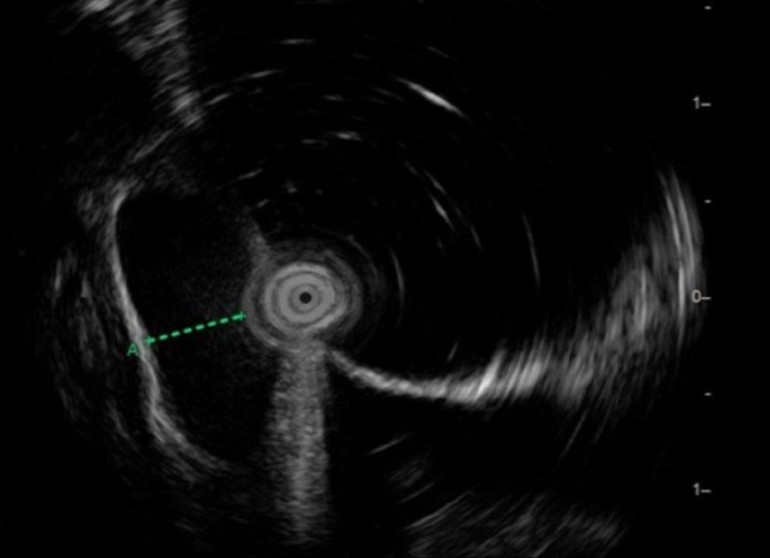

Kết quả nội soi siêu âm cho thấy khối u kích thước 1.5 x 1 x 0.7cm, nằm ở lớp cơ niêm và dưới niêm mạc, lớp cơ trơn phía dưới còn nguyên vẹn, giảm âm đồng nhất, có ranh giới rõ, không quan sát thấy vôi hóa, chảy máu.

Tính chất khối u được đánh giá chi tiết trên hình ảnh nội soi siêu âm.